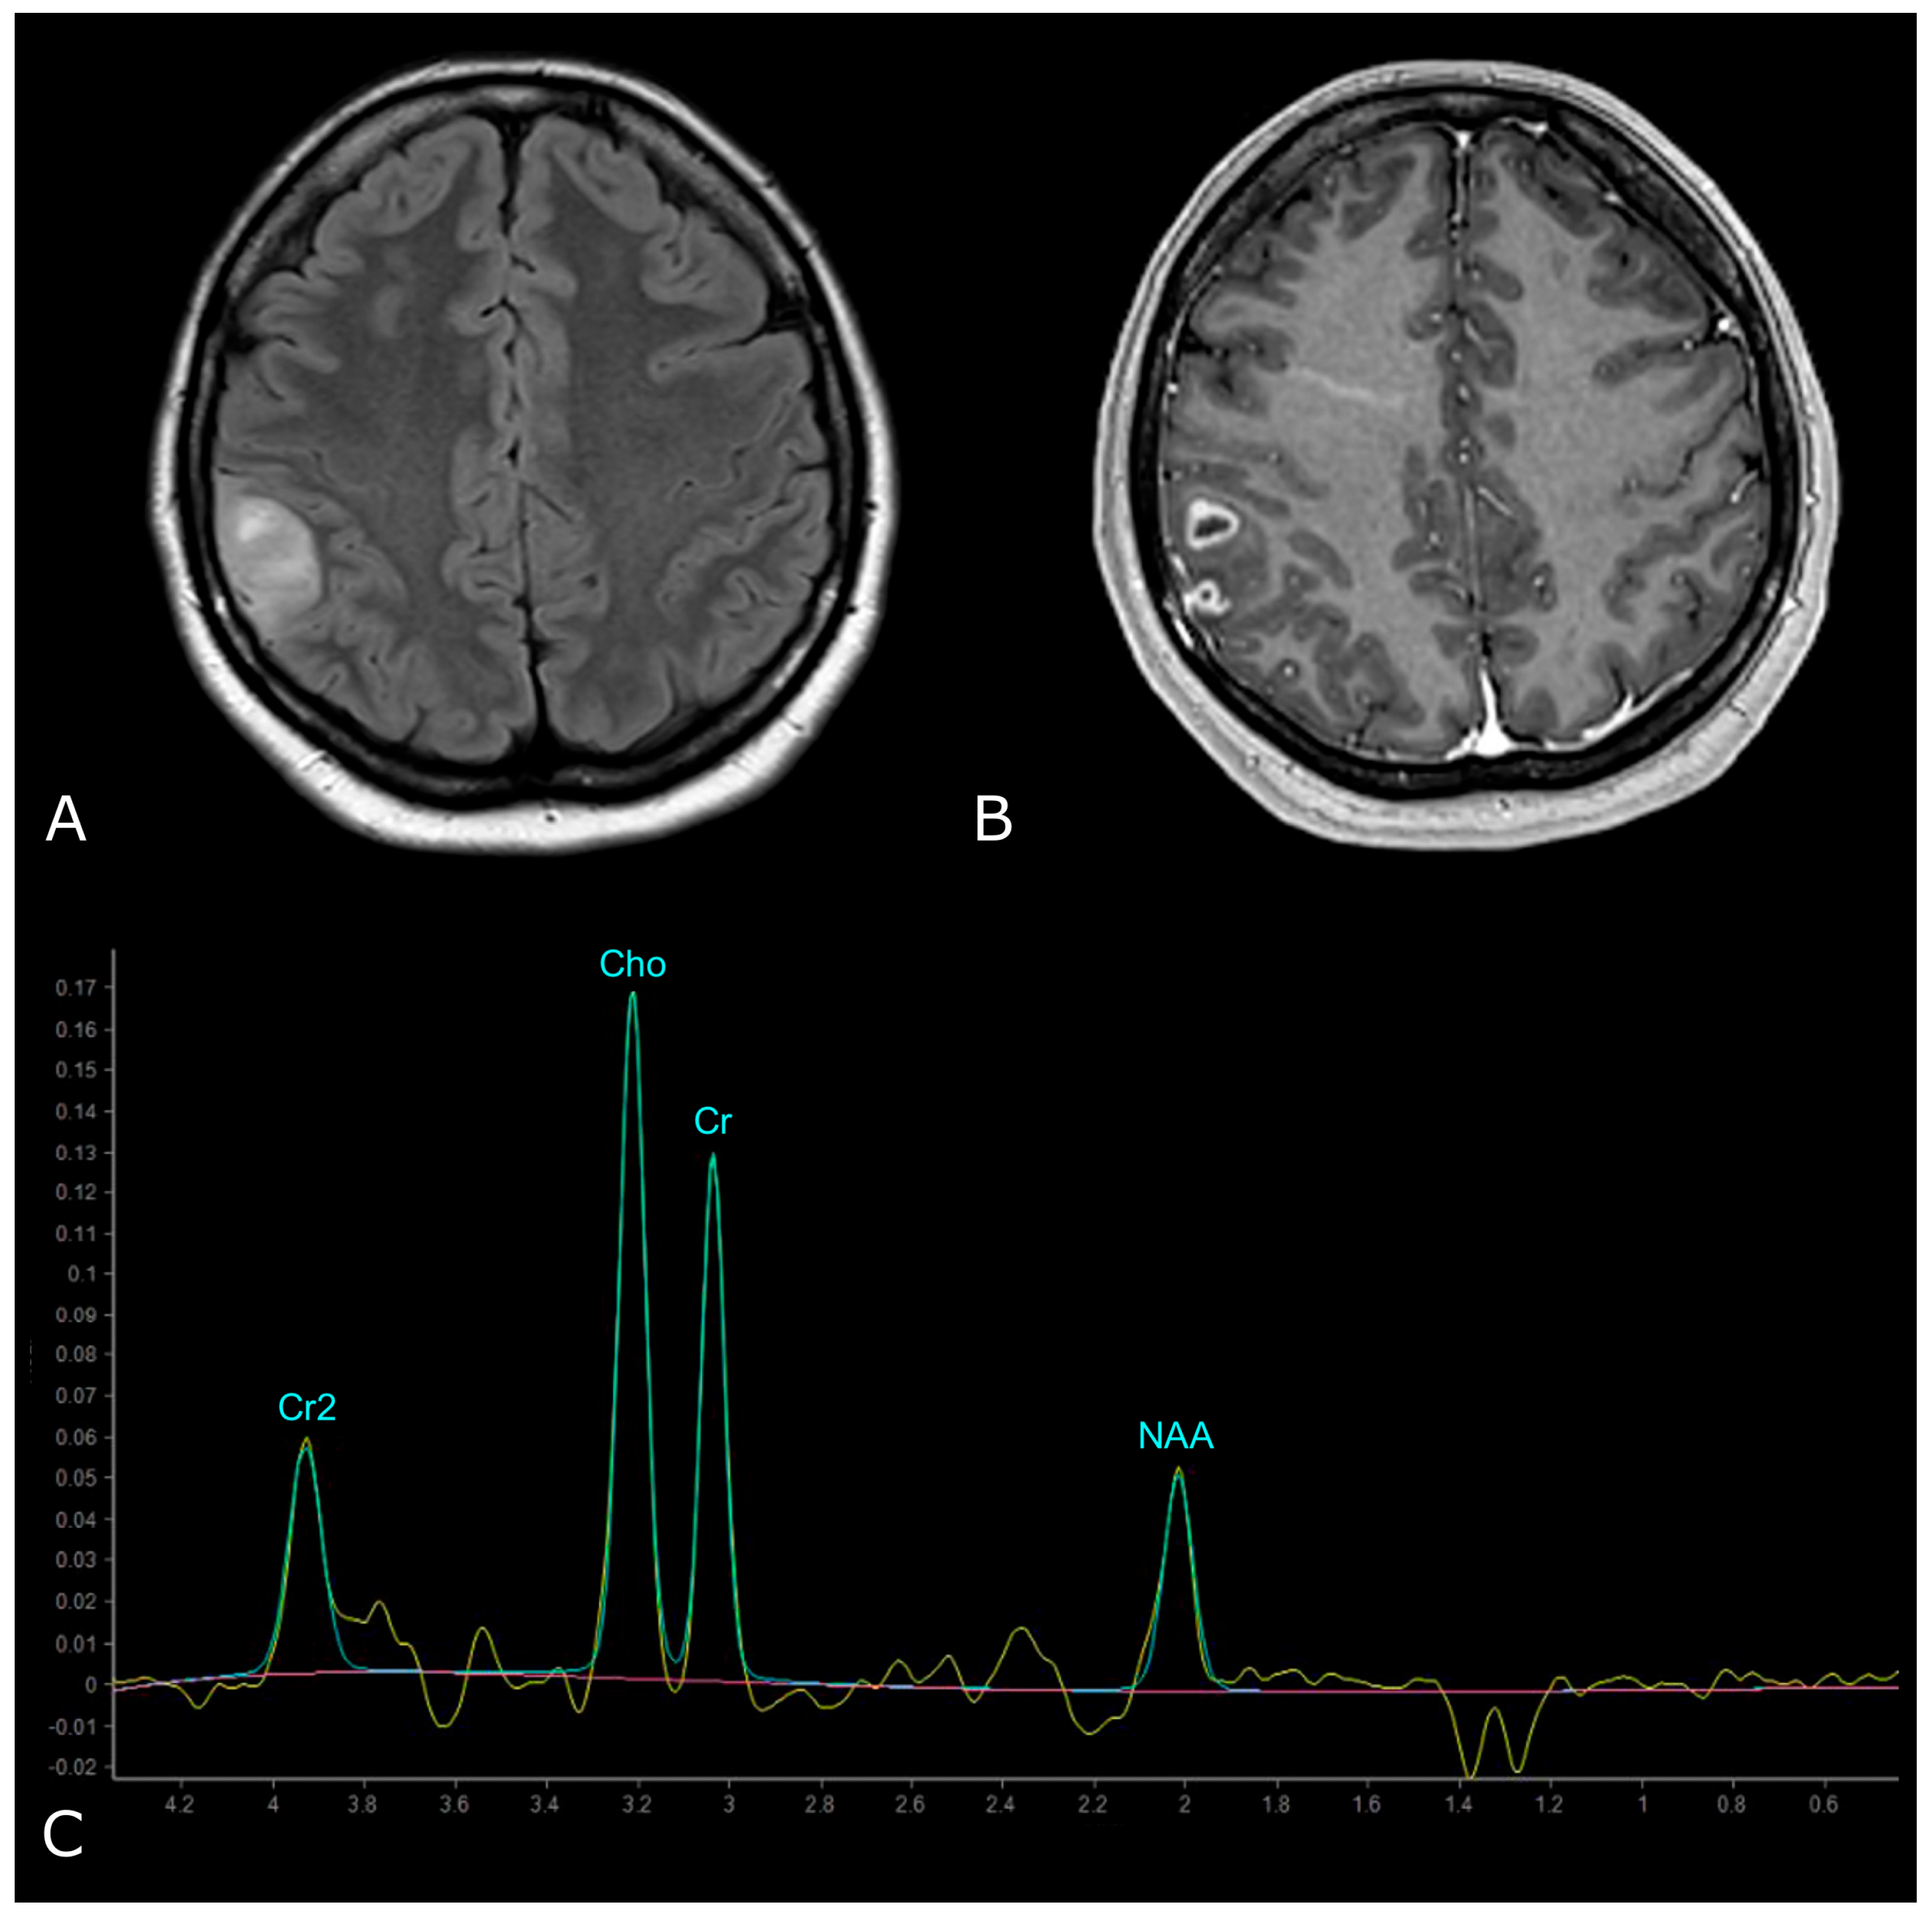

Figure 9.

MR Spectrum of LGG (SV TE 144ms). (A,B) Axial T2-FLAIR and post-contrast T1w of a left frontal low grade IDH-mut and 1p/19q-codeleted OD. (C) SV MRS demonstrates moderate Cho elevation and NAA reduction.

On the other hand, HGGs tend to have more dramatic MRS changes, including a marked increase in Cho and decrease in Cr, NAA, and mI. Thus, higher Cho/Cr and lower NAA/Cho ratios suggest HGGs as opposed to LGGs (Figure 10). To note, pilocytic astrocytomas are reported to have a low NAA/Cho ratio, despite their benign nature, and some authors have reported low Cho levels in HGGs, which may be due to the presence of necrosis [98,100].

Figure 10.

MR Spectrum of HGG (SV TE 144ms). (A,B) Axial T2-FLAIR and post-contrast T1w of a right parietal HGG, with necrotic areas; (C) SV MRS demonstrates a prominent increase in Cho and a decrease in NAA, with high Cho/Cr and low NAA/Cho ratios. Double negative peak of lactates is also present, consistent with the presence of necrosis.